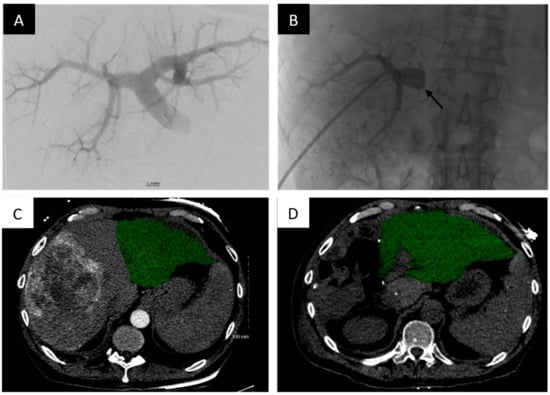

PVA particles/microparticles range in size from 150–1000 um and are widely commercially available for use. Because of their varying sizes, they are an excellent option for distal embolization. Typically, operators will use these particles in combination with coils or plugs for proximal embolization to provide complete embolization of the target portal veins (Figure 1).

Portal vein embolization of the right portal vein branch with PVA particles and coils demonstrates FLR hypertrophy. Portal vein embolization (PVE) of the right hepatic portal vein with PVA particles and coils. (A) Digital subtraction portography prior to embolization via access of the posterior division of the right portal vein. (B) Post-embolization single shot image of the right portal system embolized with PVA particles and a Nester coil (Cook Medical, Bloomington, IN, USA). (C) Axial contrast enhanced computed tomography (CT) slice demonstrating the pre-embolized liver, with the non-hypertrophied left lobe highlighted. (D) Post-PVE contrast-enhanced axial CT slice demonstrating noticeable hypertrophy of the left liver post-right PVE and hepatectomy (approximately 28 days post-resection).

In study by Camelo et al., 63 patients who received preoperative PVE with PVA particles and coils demonstrated an FLR increase from a mean value of 484 mL ± 242 to 654 mL ± 287 (p < 0.001), a mean percentage increase of 40% [38]. It should be noted that this study found a negative relation between the FLR volume before PVE and the FLR volume increase induced by PVE (R = −0.46, p < 0.001). Two out of the 64 patients (3.1%) suffered major adverse events. Ultimately, 44 patients underwent successful surgical resection (68.8%), with only one with postoperative hepatic insufficiency.